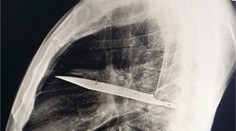

Nôž mala zaseknutá nad pravým uchom, trčala iba rukoväť.

Trojročné dievčatko vošlo do Dongchuan People’s Hospital v juhozápadnej Číne s nožom zaseknutým nad pravým uchom, píšu weby Mirror a Daily Mail.

Dievča podstúpilo kraniotómiu, pri ktorej neurochirurg bezpečne odstránil čepeľ. Stav pacientky je podľa médií stabilný a zostáva pod dohľadom.

Lekár povedal, že prežitie považuje za zázrak, ktorý pripisuje aj mäkkosti detskej lebky. Dodal, že ak by matka nôž bezhlavo vytiahla, riziko by bolo obrovské a správnym krokom bolo okamžite vyhľadať odbornú pomoc.